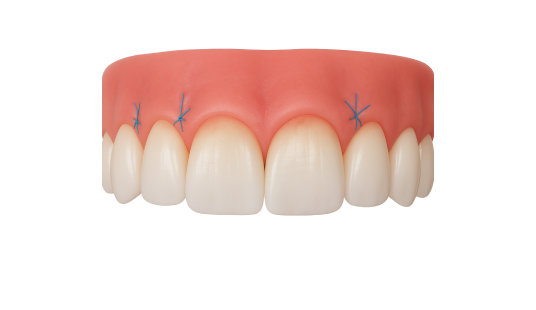

Закрытие рецессии десны. Чтобы восстановить ткани десны и защитить корень зуба, врач использует методику трансплантации мягких тканей. Лечение периимплантита. Чтобы устранить воспаление вокруг имплантата, врач тщательно очищает мягкие ткани от бактериального налета и инфицированных участков. Иногда назначается медикаментозная терапия. В случае необходимости хирург выполняет коррекцию тканей, чтобы стабилизировать имплантат и предотвратить его потерю. Пластика уздечки и слизистых тяжей. Если уздечка языка или губ укорочена, проводится коррекция. Процедура проходит под местной анестезией и длится всего несколько минут. Она позволяет устранить дискомфорт, улучшить функциональность и предотвратить развитие патологий зубного ряда и дефектов речи.